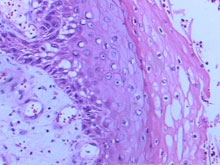

疣状癌

1948年疣状癌Ackeman首先,该病是一种高角质化鳞状细胞癌。该病的诊断取决...

活体组织病理检查(活检)